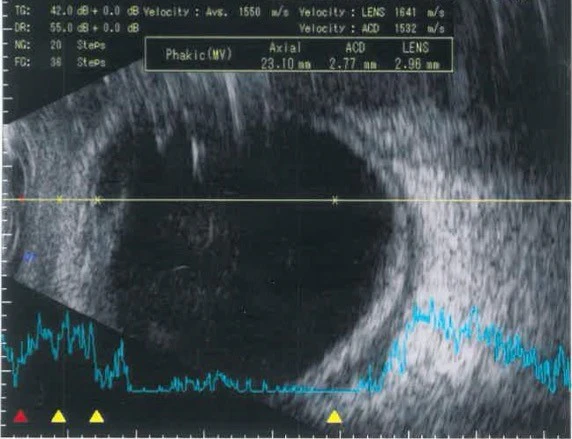

A B-scan of the right eye showed scleral thickening (Figure 2). The patient underwent a CT scan of her orbits, which revealed right-sided proptosis with intraconal fat stranding and inflammation surrounding the globe and optic nerve, consistent with scleritis and retrobulbar optic neuritis (Figure 3). Investigations, including serum ACE, treponemal serology, ANA and QuantiFERON-TB Gold, were unremarkable.

Figure 2: A B-scan of the patient’s right eye showing scleral thickening (white arrow).